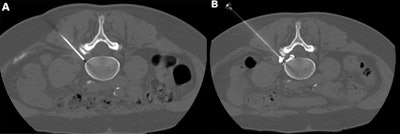

CT-guided pulsed radiofrequency (PRF) with transforaminal epidural steroid injection. A 62-year-old woman underwent PRF followed by transforaminal epidural steroid injection for sciatica due to left contained intraforaminal disk herniation at the L4-5 level. (A) A 22-gauge needle electrode with a 10-mm active tip was introduced and advanced using one 3-mm oblique axial unenhanced CT scan, which revealed that the needle tip was proximate to the target dorsal root ganglion with the lateral foraminal portal of entry. (B) Sensitive stimulation (50 Hz) PRF current with a threshold of no more than 0.2 V was used to confirm proper positioning by evoking tingling or electric pain in the dermatome that had to match the target dorsal root ganglion. Therapeutic PRF was then performed in one 10-minute session with E-dose functionality, maintaining temperature below the threshold for neural damage (42°C) and a constant voltage (45 V) (G4 RF Generator; Boston Scientific). Immediately after PRF administration, epidural spread of 0.3 mL of contrast material (350 mg of iodine per milliliter, Iomeron; Bracco) was confirmed using intermittent intraprocedural CT fluoroscopic imaging with no intravascular contrast material flow demonstration. A combination of steroid and anesthetic (1 mL lidocaine [ 20 mg/mL] and 2 mL dexamethasone [10 mg/mL]) was then injected without altering needle position to conclude the procedure. Image and caption courtesy of Radiology.Evidence to support the combined approach of these procedures is lacking, according to Napoli and colleagues. In this study, the researchers hypothesized that combining PRF and TFESI would be more effective than TFESI alone.